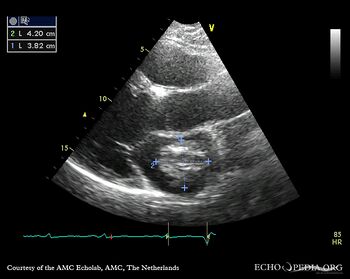

| Courtesy of: AMC Echolab, AMC, The Netherlands | |

| PLAX: dilated left ventricle, myxoma in left atrium | PLAX: dimensions of myxoma |